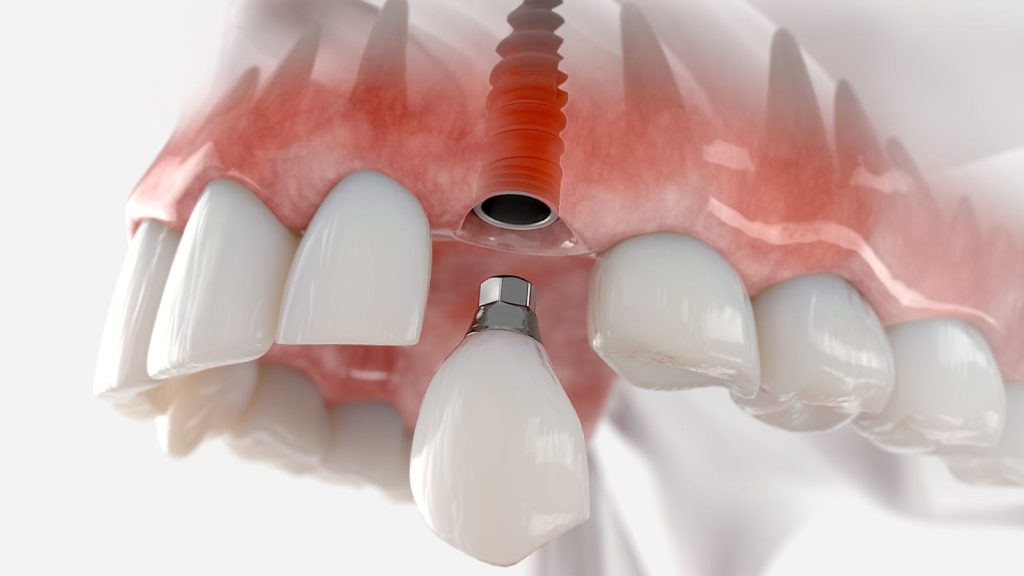

העמסה מיידית היא חיבור שיקום זמני (לרוב גשר מוברג) אל השתלים בתוך 0–72 שעות מההשתלה, כך שהמטופל יוצא עם שיניים קבועות-זמניות באותו יום. לפי מסמכי הקונצנזוס של ITI, זהו פרוטוקול מוכר וקלינית בר-ביצוע כאשר מתקיימים תנאי יציבות ראשונית ומדיניות ריכוך עומסים נכונה.

הפרוטוקול הכירורגי-שיקומי בקצרה (One-Day)

- אבחון ותכנון דיגיטלי: סריקת CBCT/סורקים תוך-פה, תכנון מיקומי שתלים לשיקום מוברג, שקילת זוויות/מולטי-יוניטים, ותכנית אוקלוזלית לריכוך עומסים.

- השתלה והשגת יציבות: שאיפה ל-IT ≥30–45 N·cm ו-ISQ סביב 70+; אם היציבות לא מספקת – עוברים להעמסה מוקדמת/מאוחרת.

- שיקום זמני מוברג באותו יום: גשר PMMA/קומפוזיט מחוזק (או הדפסה/חריטה מיידית), עם אוקלוזיה מגבילה (ללא מגעים אקסצנטריים חדים, דיאטה רכה).